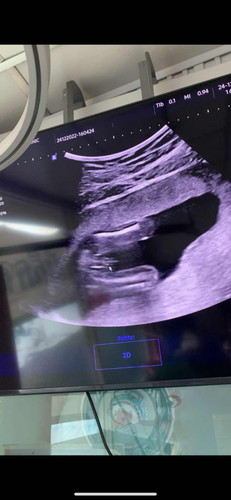

ขอถามแม่ๆหน่อยคะผู้ชายรึผู้หญิง😂แต่หมอว่าผู้ชาย#ท้องแรกคะ

ถ้าเป็นภาพนี้ละค่ะเเม่ๆมองไม่ออกจริงๆค่ะ

ชัดแจ๋วเลยค่ะน้องมีจู๋😂

ผช ค่ะ นั่นจู๋น้อง😂😂

จู๋โชว์เลยค่ะแม่😛

อันนี้ตอนกี่วีคค่ะ

14วีคจ้า

ผู้ชายค่ะ ชัดแจ๋ว

น่าจะเป็นชาย